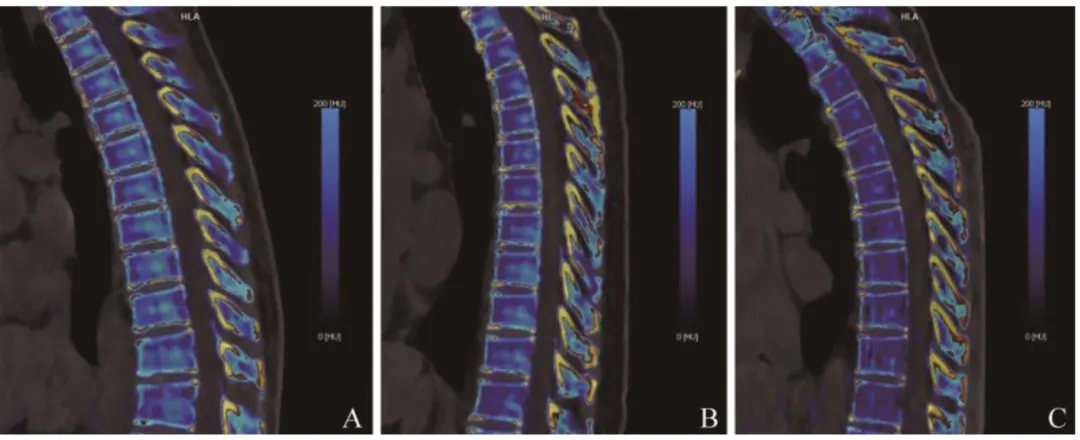

本研究最终纳入75例患者,431个胸椎进行VCI参数分析。75例患者中,男30例,女45例,平均年龄(71.8±9.6)岁。根据T值将患者分为3组:骨量正常组18例101个胸椎,骨量减少组35例203个胸椎,骨质疏松组22例127个胸椎(图2)。3组患者年龄、性别、BMI差异均有统计学意义(P均<0.05)。骨量正常组、骨量减少组、骨质疏松组患者年龄依次增加,BMI相应地降低(表1)。PCCT低剂量胸部扫描容积剂量指数为0.81~1.44 mGy,平均(1.08±0.27)mGy;剂量长度乘积为31.20~48.60 mGy·cm,平均(42.00± 11.27)mGy·cm。

图2  骨量正常、骨质减少和骨质疏松患者VCI图像。A~C分别为骨量正常、骨量减少及骨质疏松患者VCI。VCI为虚拟钙成像